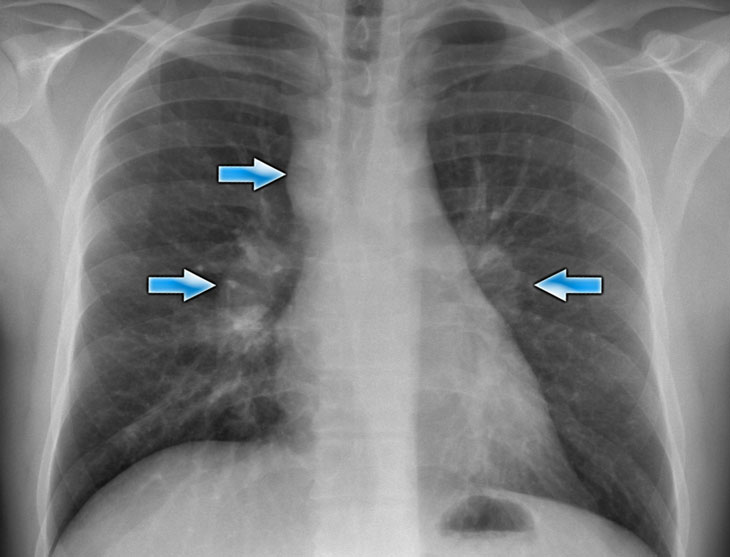

Hilar enlargement - case 1

In this case there is an enlarged hilar shadow on both sides.

This could be the result of enlarged vessels or enlarged lymph nodes.

A very helpful finding in this case is the mass on the right of the trachea.

This is known as the 1-2-3 sign in sarcoidosis, i.e. enlargement of left hilum, right hilum and paratracheal.

Here some more examples of sarcoidosis.

Click image to enlarge.

1. Lymphadenopathy and groundglass appearance of the lungs

2. Lymphadenopathy, 1-2-3 sign

3. Bulky lymphadenopathy

4. 1-2-3 sign

5. Nodular lung pattern, no lymphadenopathy

6. Hilar and paratracheal lymphadenopathy